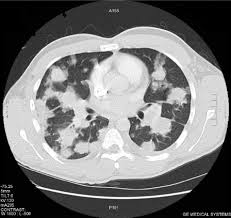

How To Know If Testicular Cancer Has Spread To Lungs - Royal Marsden Hospital Staging Of Testicular Cancer Download Table / Stage iii (stage 3 testicular cancer):. The tumour has only spread to the abdominal lymph nodes or the lungs or both. Testicular cancer begins in your testes, the male reproductive organ. If cancer cells have spread to your lymph nodes (or beyond your lymph nodes to another part of the body), symptoms may include: Shortness of breath, chest pain, or a cough (even coughing up blood) may develop from cancer spread in the lungs. At least one tumour marker level is moderately high.

Swelling of 1 or both legs or shortness of breath from a blood clot can be symptoms of testicular cancer. The tumour has only spread to the abdominal lymph nodes or the lungs or both. This is how doctors can tell that it is cancer that has spread from another part of the body. The tumour has spread to organs other than. The primary tumour is in the area between the lungs.

Treatment For Stage 4 Testicular Cancer Onco Com from onco.com This is testicular cancer which has spread to the lungs. So when testicular cancer spreads to the lung (or any other place), it's still called testicular cancer. A blood clot in a large vein is called deep venous thrombosis or dvt. As with other forms of cancer, testicular cancer can spread, or metastasize, to other areas of the body. In the later stages of development, testicular cancer can even spread to the lungs, brain or liver. Additional areas where testicular cancer may metastasize include the: I know that sounds obvious but it is an important distinction. Testicular cancer that has spread to other parts of the body may reveal itself in a number of ways.

His cancer had spread to his lungs, stomach and brain. Swelling of 1 or both legs or shortness of breath from a blood clot can be symptoms of testicular cancer. But most of the time they're on the edges of your lungs or in the lower lobes. If testicular cancer spreads, it can spread to the following: Liver is pretty close to the lungs. If it has spread to the lungs you may have a cough or feel breathless. Metastatic cancer has the same name as the primary cancer. As with other forms of cancer, testicular cancer can spread, or metastasize, to other areas of the body. The m in the tnm system describes whether the cancer has spread to other parts of the body, called distant metastasis. Once the cancer has spread to the liver, the prognosis and survival rate from the disease can drop significantly. The primary tumour is in the area between the lungs. It's not called lung cancer unless it starts from cells in the lung. The nature (cell type) of the metastatic.

How do you know if testicular cancer has spread? The tumour has spread to organs other than. When the disease has reached stage 2, the cancer will have spread into the patient's lymph system (the retroperitoneal lymph nodes are usually he first to be affected) and may spread to the kidneys. The most common place for testicular cancer to spread to is nearby lymph nodes in your tummy (abdomen) or lungs. It may have spread to the lungs or lymph nodes, but has not spread to anywhere else in your body. Testicular cancer that has spread to other parts of the body may reveal itself in a number of ways. It rarely spreads to other organs in the body. If the cancer has spread to the lungs sometimes testicular cancer spreads to the lungs. Certain types of testicular cancer are more likely to spread than others. When testicular cancer spreads, it most commonly spreads to the lung and the lymph nodes of the chest, pelvis, and the base of the neck. A blood clot in an artery in the lung is called a pulmonary embolism and causes shortness of breath. Additional areas where testicular cancer may metastasize include the: The primary tumour is in the area between the lungs.

Which treatment your doctor will choose to treat it is based on the type of cancer you have and if it has spread. It's not called lung cancer unless it starts from cells in the lung. There is no poor prognosis grouping for seminoma testicular cancer. Testicular cancers at this stage have spread to distant lymph nodes or organs. A blood clot in an artery in the lung is called a pulmonary embolism and causes shortness of breath. This is how doctors can tell that it is cancer that has spread from another part of the body. And you might have one tumor in one lung or many tumors in both lungs. So when testicular cancer spreads to the lung (or any other place), it's still called testicular cancer. The tumour has only spread to the abdominal lymph nodes or the lungs or both. These are some reasons of why the metastasis of lung cancer to the liver is quite common. I know that sounds obvious but it is an important distinction. With proper treatment, even more advanced stage 3 testicular cancer can be cured. Lymph nodes are glands that make up your immune system.